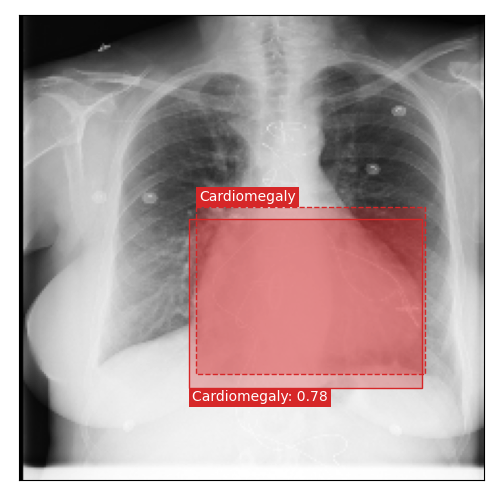

Qualitative Results

As shown in Fig. 4 Loc-ADPD detects cardiomegaly almost perfectly, as it is always exactly localized at one anatomical region. Other pathologies are detected but often with too large or too small boxes as they only cover parts of anatomical regions or stretch over several of them, which cannot be completely corrected using WBF. Detection also works well for predicting several overlapping pathologies. For qualitative comparisons between Loc-ADPD and MIL-ADPD, we refer to Appendix 0.B.